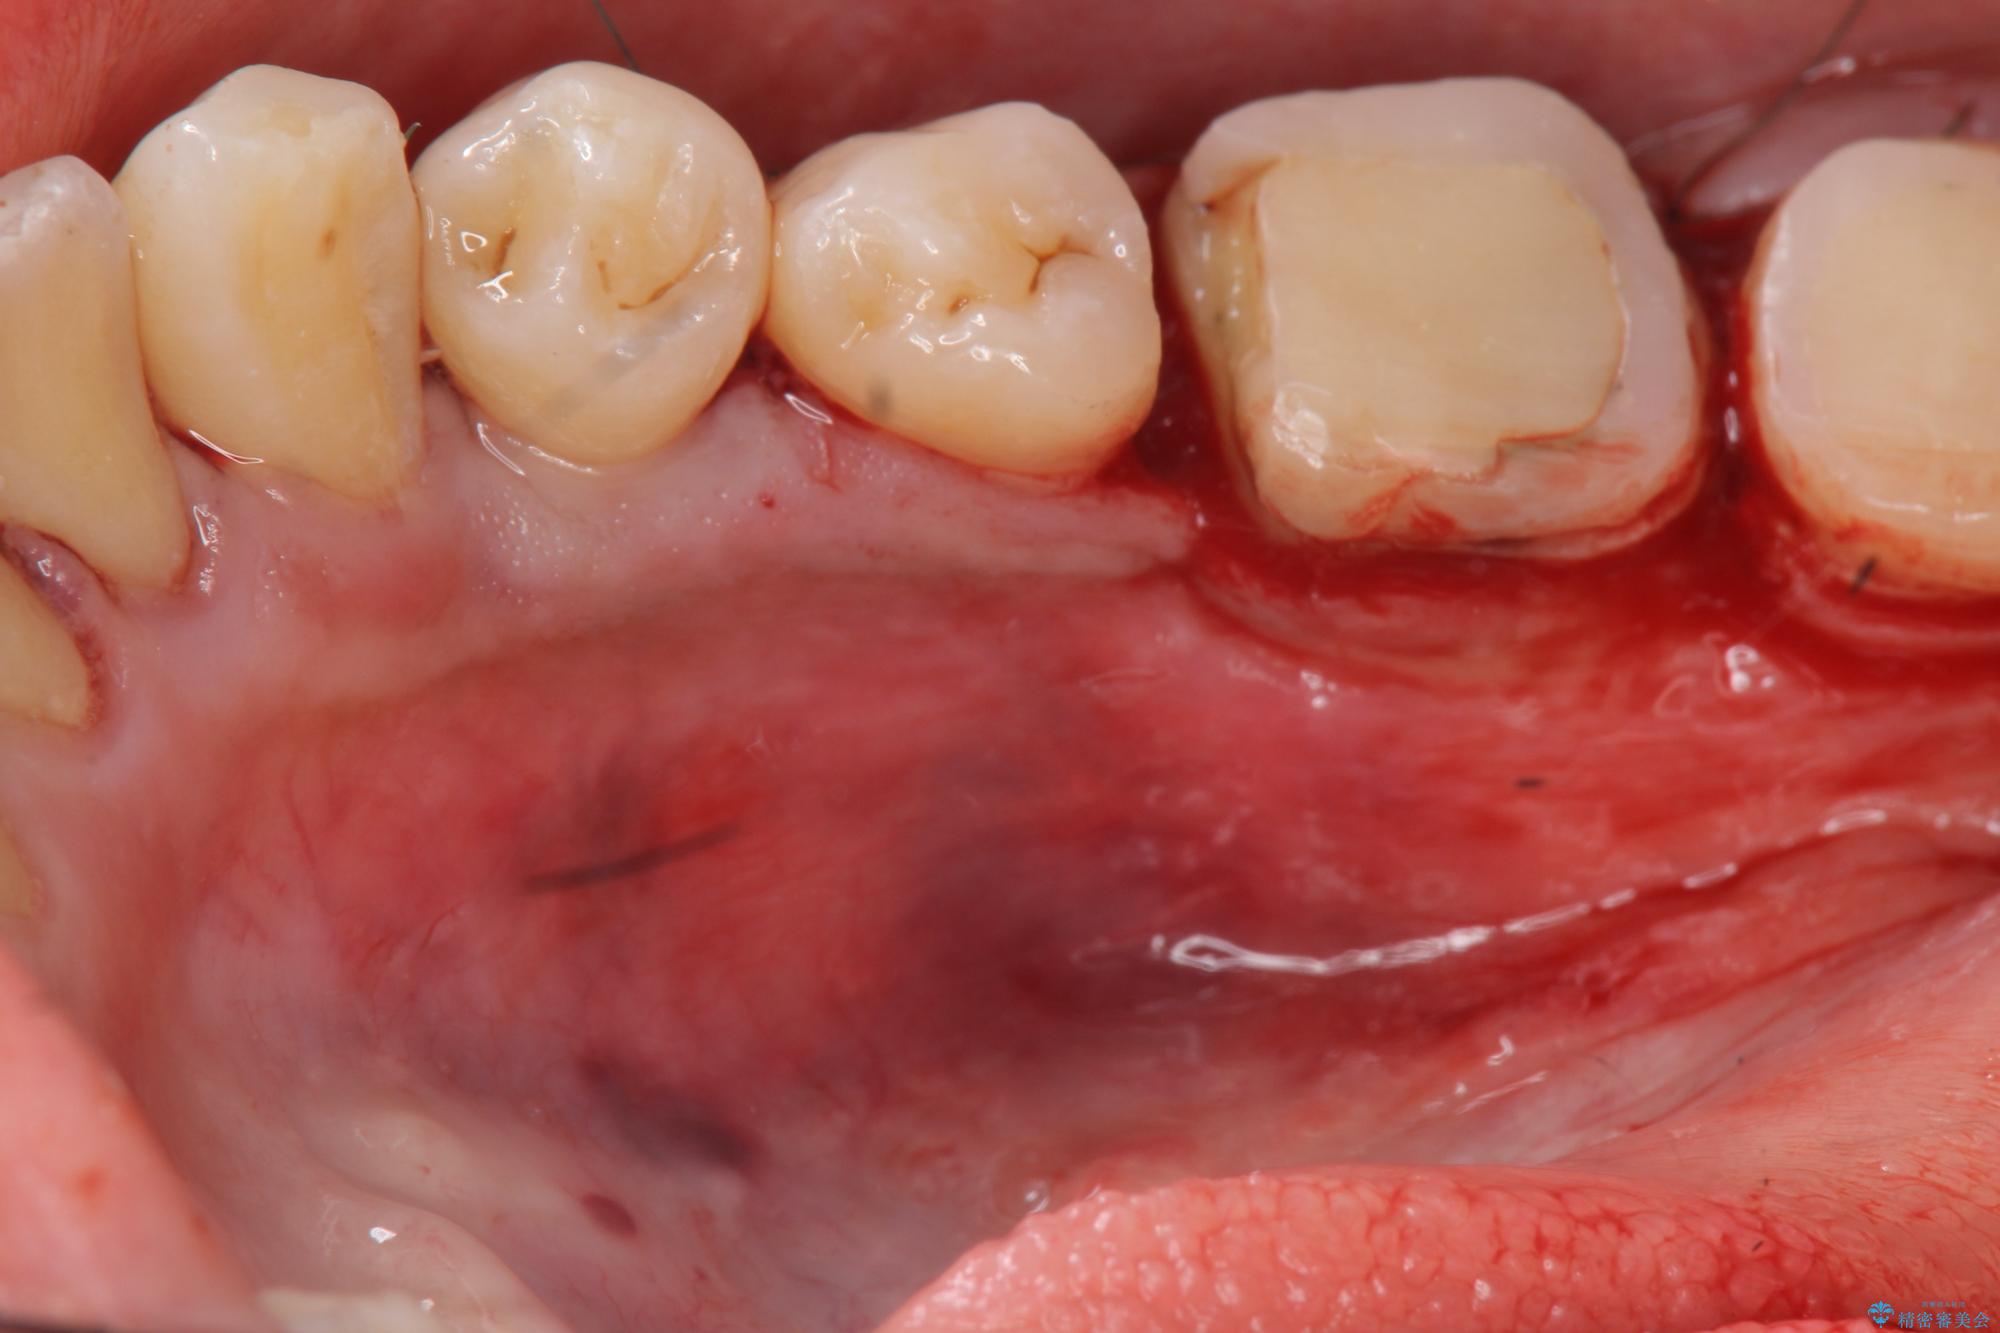

歯周外科を行うことで、歯ぐきの位置を下げ歯の高さを作り出し安定したクラウンの装着が可能となります。また同時に舌の邪魔となっていた骨隆起の除去を行うこととしました。

歯周外科に際しては、静脈内麻酔を行うことでほとんど記憶のないうちにリラックスした状態で受けていただくことができました。